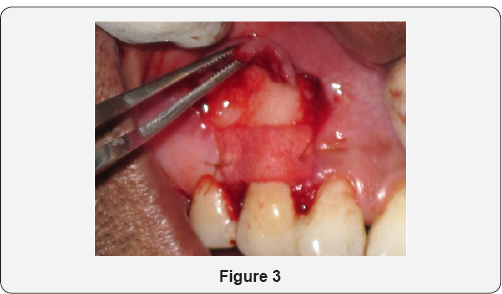

Patient aged 34 years reported to the department of Periodontology with the complaint of long corner tooth with sensitivity. On clinical examination, gingival recession was observed on maxillary right canine (Figure 1). Diagnosis was made as Miller's Class I gingival recession with 13. Coronally advanced flap with alloderm with microsurgical approach was planned. Patient's consent as well as ethical clearance was obtained prior to the surgical intervention. Following administration of local anesthesia, the tooth with the recession was root planed. A split-thickness flap with two vertical releasing incisions with micro scalpels was raised with microelevaters, and the papillae were de-epithelialized (Figure 2). Alloderm was measured, cut and rehydrated before suturing it with chromic gut 5-0 covering the defect as shown in Figure 3. The flap was coronally moved and secured to the de-epthelialized papillae over the alloderm with interrupted sutures (5-0 black braided silk) as shown in Figure 4. Pressure was applied before placing the periodontal dressing on surgical wound. Sutures were removed on 10th day and healing was found to be satisfactory (Figure 5). Healing is generally uneventful in minimally invasive surgery. Patient was evaluated after 3 months; there was 100% coverage of a denuded root with satisfactory gingival thickness and color match with microsurgical reconstruction of lost gingival (Figure 6).